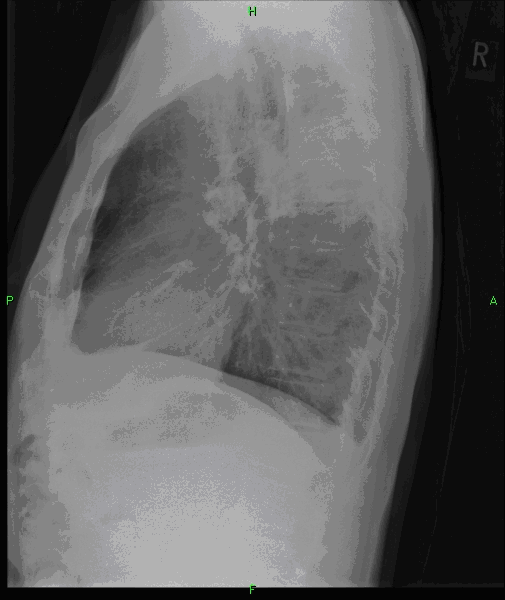

4: Miliary pattern: sarcoidosis, CT, lung window. Axial image and sagittal reformat.

A 67 year old female suffering from COPD. Bilateral rough branching interstitial widening and patchy, miliary nodules with perihilar dominance along the bronchovascular fibres and the fissures.